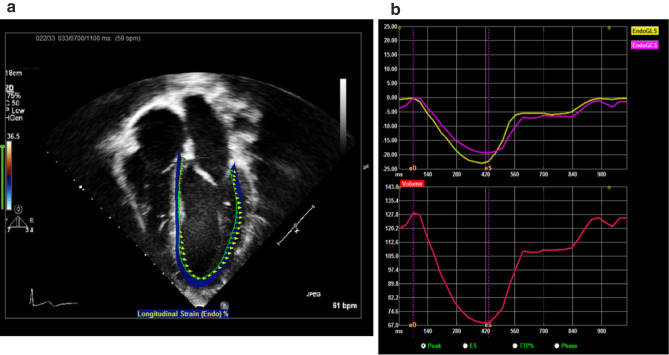

Cirrhotic cardiomyopathy is a complication of cirrhosis resulting in cardiac dysfunction. It remains poorly characterized in children. The aim of this study was to assess relationship of pre-liver transplant (LT) conventional and novel parameters of biventricular function with post-LT clinical course. This is a retrospective study of pre-LT echocardiograms performed on patients < 18 years of age with cirrhosis at a single center, who received a LT. Demographic, clinical, and echocardiographic data were collected. Speckle tracking echocardiography (STE) analysis was performed by a single observer using TomTec system. Descriptive data were expressed as mean (SD) and number (%). The relationship between clinical data and echocardiographic variables were assessed using Spearman correlation coefficient. Significance was set at < 0.05. Thirty-five patients (median age 6.5; IQR 14.2 years) underwent LT between 2010 and 2020. Pre-LT diagnosis was biliary atresia in 14 (40%) patients and 7 (20%) patients were listed as status 1A/1B. Their median natural pediatric/model end-stage liver disease score was 13 (IQR 9). Their pre-LT echocardiogram showed normal left ventricular systolic (LV) function by ejection fraction and strain parameters. Right ventricular (RV) function was abnormal in 74% of patients as measured by RV GLS (23 ± 3%). There was correlation between echocardiographic parameters with pre-transplant clinical disease and post-operative LT course (length of stay and duration of mechanical ventilation). Children undergoing liver transplant have RV dysfunction as evidenced by abnormal RV GLS on STE. There is echocardiographic parameter correlation between clinical liver disease and post-LT clinical course. This evidence highlights the importance of using novel technology like STE in assessment of children undergoing evaluation for liver transplant.